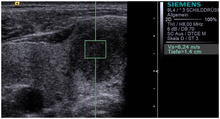

![]() Conventional ultrasonography (lower image) and elastography (supersonic shear imaging; upper image) of papillary thyroid carcinoma, a malignant cancer. The cancer (red) is much stiffer than the healthy tissue. | |

Supersonic Shear Imaging (SSI)

Supersonic Shear Imaging (SSI)[7][8] gives a quantitative, real-time two-dimensional map of tissue stiffness. SSI is based on SWEI: it uses acoustic radiation force to induce a 'push' inside the tissue of interest generating shear waves and the tissue's stiffness is computed from how fast the resulting shear wave travels through the tissue. Local tissue velocity maps are obtained with a conventional speckle tracking technique and provide a full movie of the shear wave propagation through the tissue. There are two principal innovations implemented in SSI. First, by using many near-simultaneous pushes, SSI creates a source of shear waves which is moved through the medium at a supersonic speed. Second, the generated shear wave is visualized by using ultrafast imaging technique. Using inversion algorithms, the shear elasticity of medium is mapped quantitatively from the wave propagation movie. SSI is the first ultrasonic imaging technology able to reach more than 10,000 frames per second of deep seated organs. SSI provides a set of quantitative and in vivo parameters describing the tissue mechanical properties: Young’s modulus, viscosity, anisotropy.

This approach demonstrated clinical benefit in breast, thyroid, liver, prostate and musculoskeletal imaging. SSI is used for breast examination with a number of high-resolution linear transducers.[9] A large multi-center breast imaging study has demonstrated both reproducibility [10] and significant improvement in the classification[11] of breast lesions when shear wave elastography images are added to the interpretation of standard B-mode and Color mode ultrasound images.